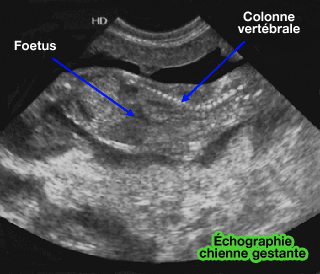

Avant trois semaines, il est difficile de détecter la grossesse du

point de vue échographique chez la chienne.

On peut prévoir le moment de la mise bas par deux mesures : le diamètre bipariétal et le diamètre de l'abdomen (échographie de gestation).